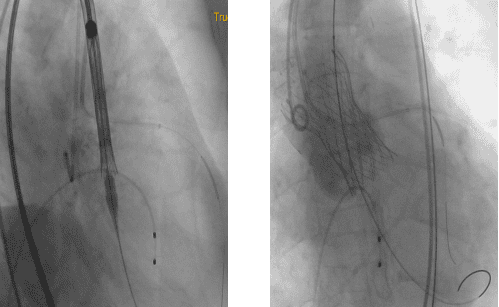

近日,南华大学附属第二医院成功为一名72岁的女性患者进行了经导管主动脉瓣置换术(TAVR)。患者体重38kg,因胸闷、气促2月余,加重7天到经诊断为心脏瓣膜病、主动脉瓣重度狭窄、心功能IV级。 前期经积极的药物治疗,但患者主动脉瓣重度狭窄并少中量返流,二、三尖瓣少中量返流,肺动脉高压,左心功能严重减低(26%)且左冠开口位置偏低,定位一旦不精准,整个左冠闭塞,后果是灾难级的。因患者衰竭状态实在不能承受外科SAVR。医院第一时间组织院内外专家进行MDT(多学科会诊)充分讨论,决定开展经导管主动脉瓣置换术(TAVR)进行治疗,并制定详细的手术方案。

术中,采用了两个新技术保护左冠;“烟囱”技术和对合缘对齐技术,同时邀请ECMO全程为手术护航,一旦出现循环崩溃等紧急情况时迅速提供体外膜肺氧合支持,保障患者生命体征。在麻醉科、心外科、普通外科血管外科专业、超声心动图室等的支持下经过团队的合作,术后主动脉跨瓣压差显著降低,无明显瓣周漏,左室射血分数即刻得到改善,术前低血压状态逐渐改善,恢复到同龄人状态。

通过多学科的紧密合作,充分发挥了各自的专业优势,成功开展了医院首例经导管主动脉瓣置换术,患者术后第2天下床,术后3天出院。